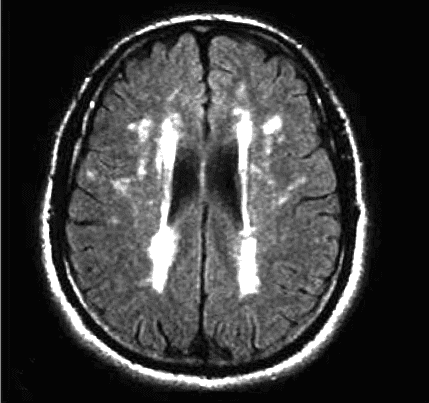

The progression of leukoaraiosis tends to follow a general pattern. Initially, periventricular lesions towards the limit (caps) of the lateral ventricles (Fig. 1) are observed spreading around them, in relation to the severity of the phenomenon, (Fig. 2).

As we have mentioned, Leukoaraiosis refers to alterations that can be detected through Computerized Axial Tomography (CAT) and brain Magnetic Nuclear Resonance (MRI) images which consist of areas of hypodensity or hyperintensity, respectively.

Of these two, the most widely used technique for the assessment of Leukoaraiosis is the brain Nuclear Magnetic Resonance imaging including T2-weighted and FLAIR sequences.